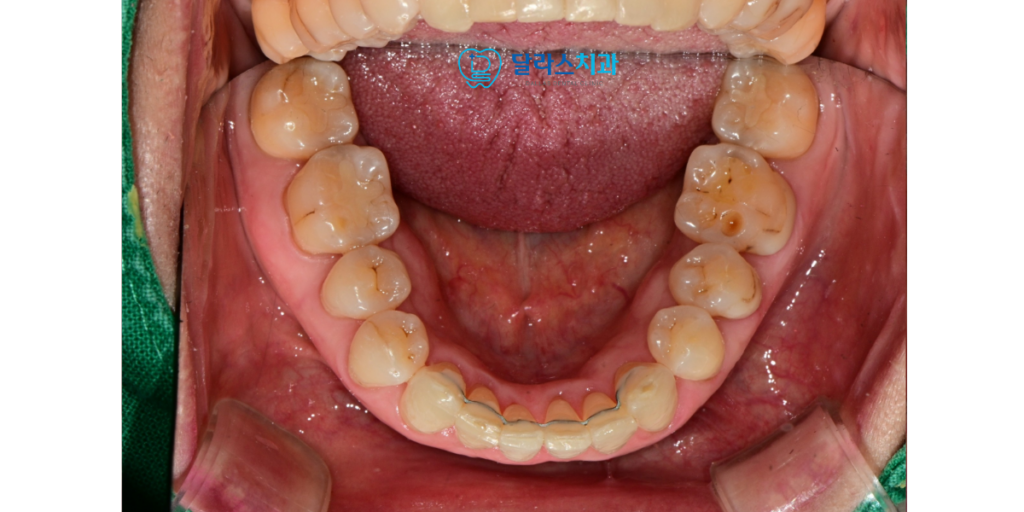

환자분께서는 세월이 흐르며 아래쪽 앞니들이 점점

겹쳐지는 현상으로 인해 불편함을 느끼고 계셨습니다.

검진 결과 하악 앞니 부위에 전형적인 치열 겹침 현상이 진행되고 있었으며

이로 인해 해당 부위의 잇몸 관리가 원활하지 않아 염증이 반복되는 상태였습니다.

저희는 환자분의 연령과 일상생활의 편의성을 고려하여

미세한 튜브 형태의 장치를 이용한 부분 교정을 제안해 드렸습니다.

먼저 하악 부위에 교정 장치를 부착하여 겹쳐진 치아들을 가지런히 펴는 작업을 시작하였습니다.